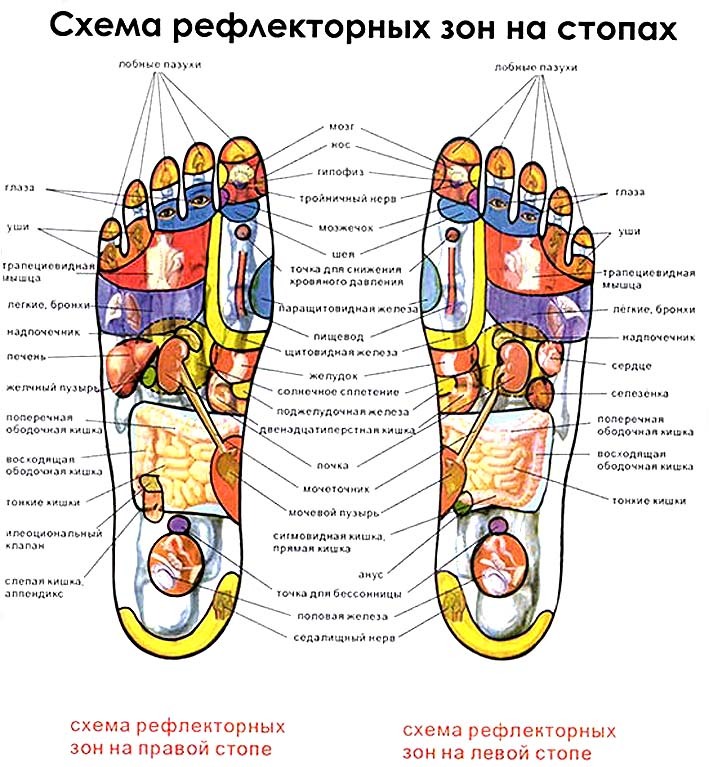

Возможные причины болей в ноге ниже колена и рекомендации